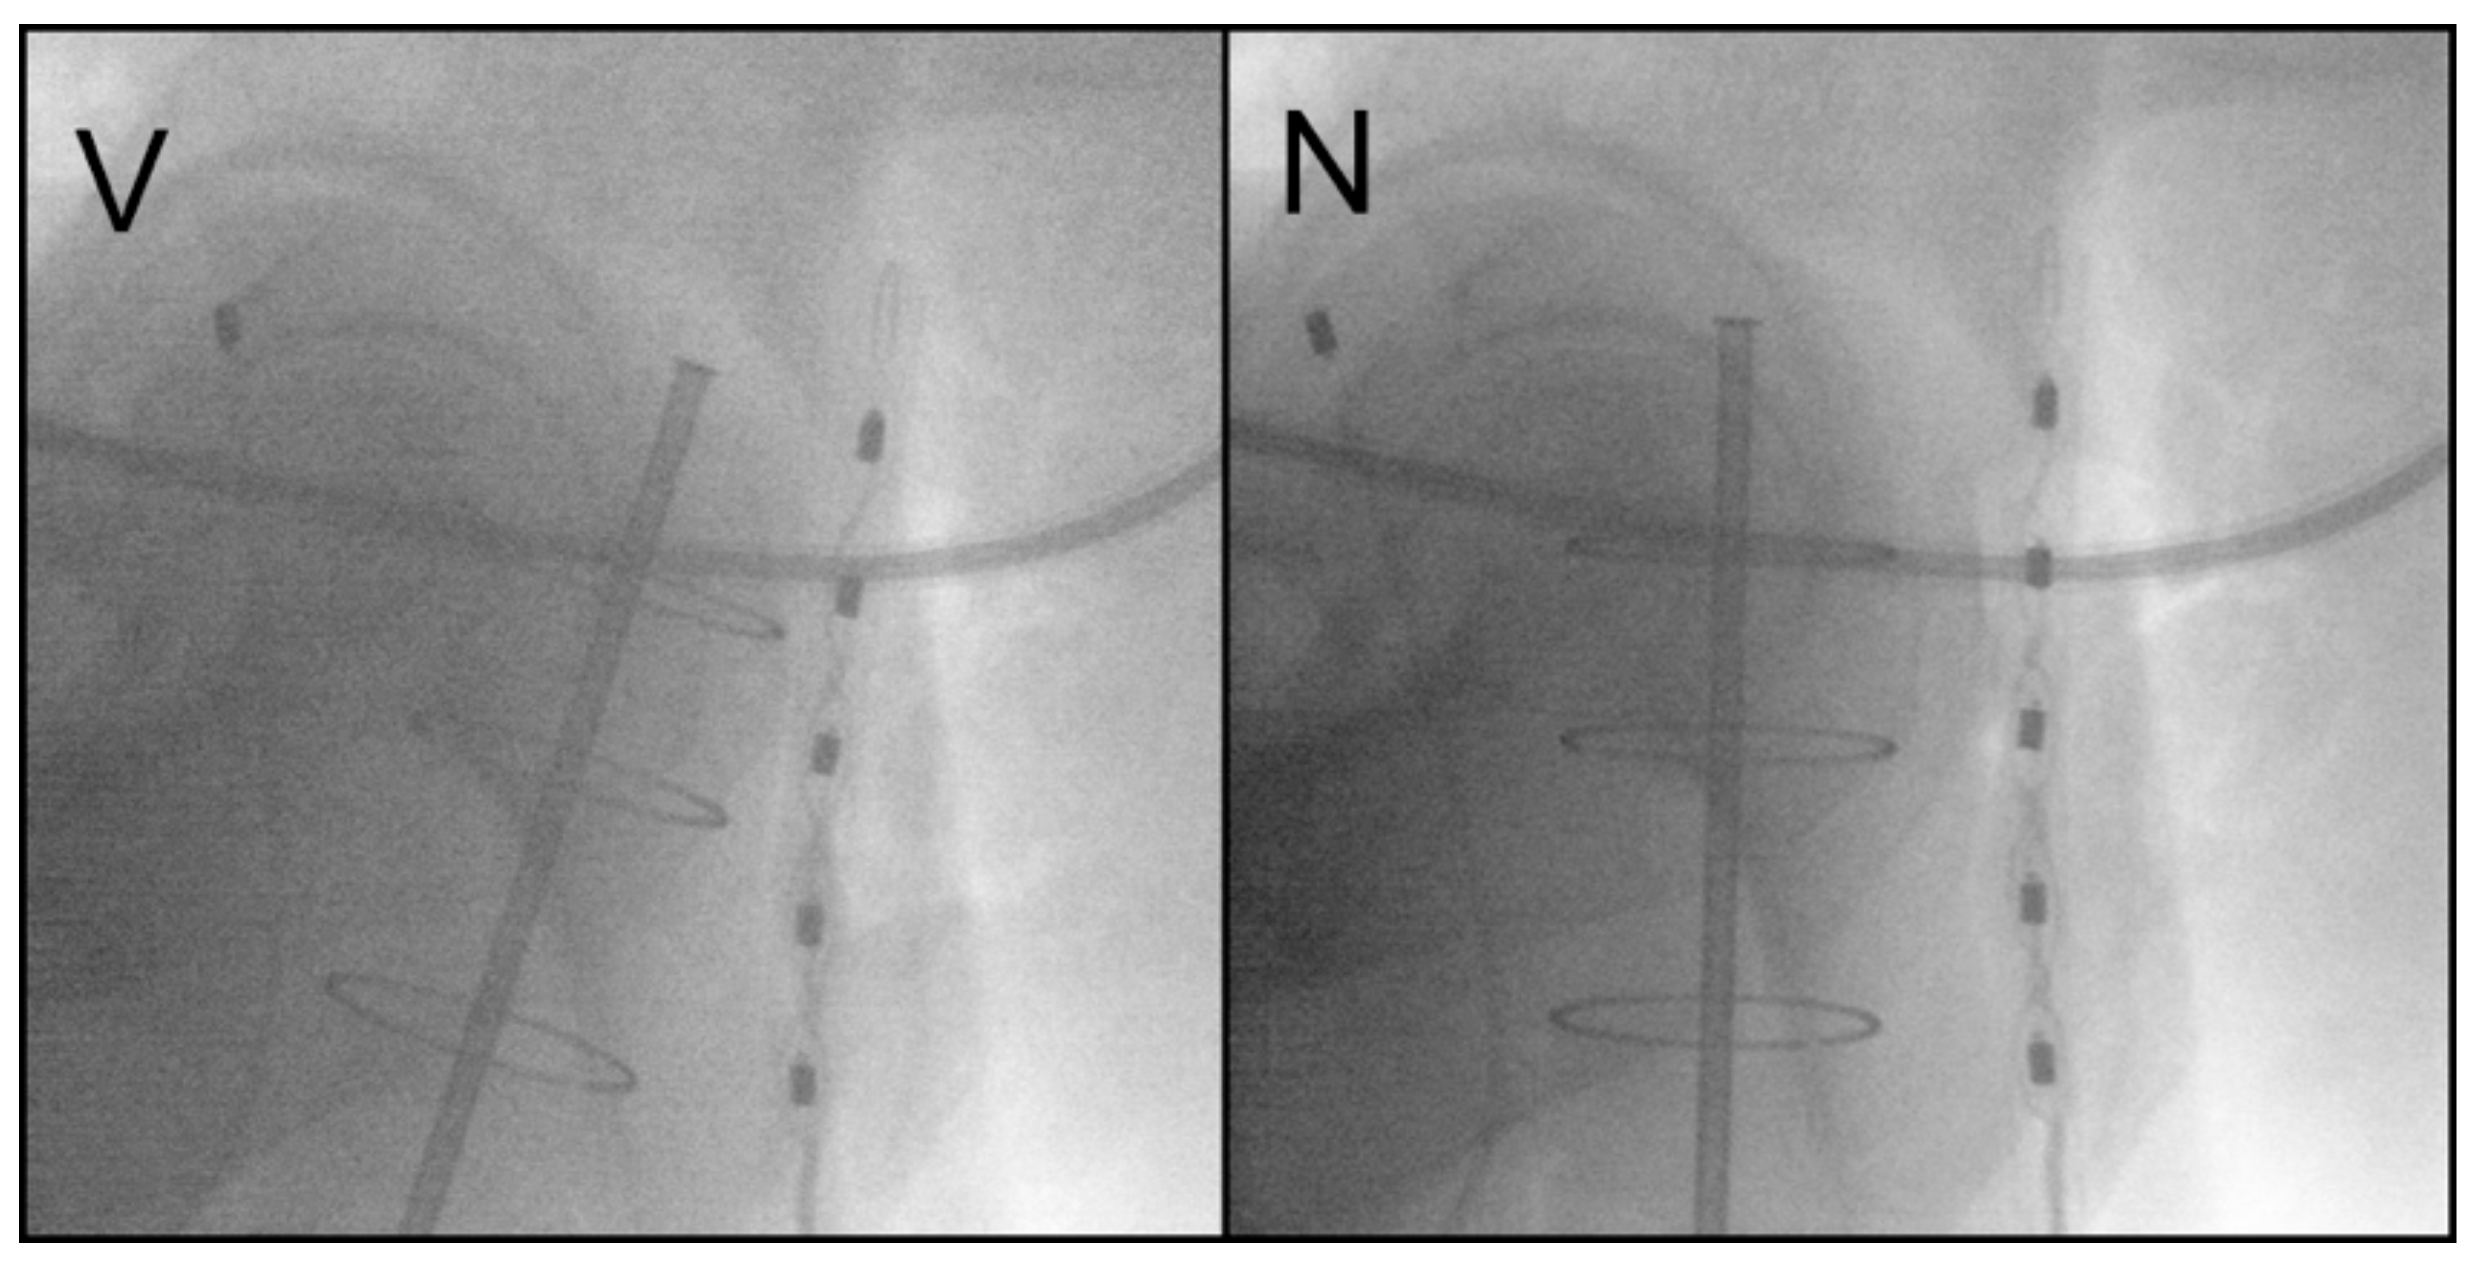

2.2. Vaginal Brachytherapy